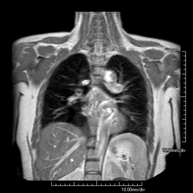

- RM Mediastino

Prueba diagnóstica no invasiva que consiste en la obtención de imágenes de alta definición anatómica del mediastino mediante el empleo de un campo electromagnético y ondas de radio (con un emisor y un receptor). No utiliza radiación ionizante. El mediastino es la parte central de la caja torácica que incluye el timo, los grandes vasos (aorta torácica, vena cava inferior y superior, etc.), el corazón, la tráquea y los bronquios principales, ganglios linfáticos mediastínicos e hiliares, el esófago, etc. Está especialmente indicada en lesiones mediastínicas para diferenciar si son quísticas o sólidas, en el diagnóstico diferencial de las lesiones del mediastino anterior, etc. En ocasiones se deberá emplear contraste paramagnético (Gadolinio) para completar el estudio.

- RM Tórax

Prueba diagnóstica no invasiva que consiste en la obtención de imágenes de alta definición anatómica del tórax mediante el empleo de un campo electromagnético y ondas de radio (con un emisor y un receptor). No utiliza radiación ionizante. Está indicada en aquellas lesiones pulmonares en las que debe descartarse si existe infiltración del mediastino o de la pared torácica, para diferenciar si una lesión torácica es sólida o quística, etc. En ocasiones se deberá emplear contraste paramagnético (Gadolinio) para completar el estudio.